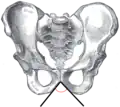

Angle sous-pubien féminin

Angle sous-pubien masculin